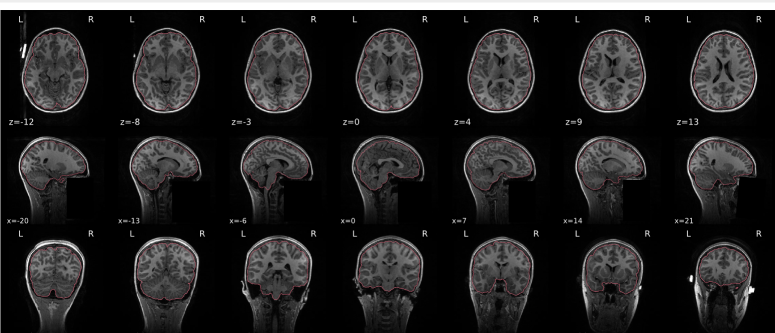

T1w skull stripping

Skull stripping is the process separating the brain (cortex and cerebellum) from the skull. The red line follows the outline of the brain and it separates it from the skull.

Example of a bad subject

- There are skull stripping errors, such as portions of the brain missing, or too much of the skull retained

- NOTE: check all the images (slices) in the report. If only one image (slice) looks problematic, it is possible that the subject is okay and it is just a visual issue in that particular screenshot

Summary

| Good | Bad |

|---|---|

| The brain is fully inside the red line | Structures like the cranium or the eyes are inside the red line |

| No important brain structures are outside of the red line red line follows the natural outline of the brain | Important brain structures are missing inside of the red line |

-> if only one slice is problematic, it could be an issue related to the visual depiction of the data instead of an issue related to the test subject